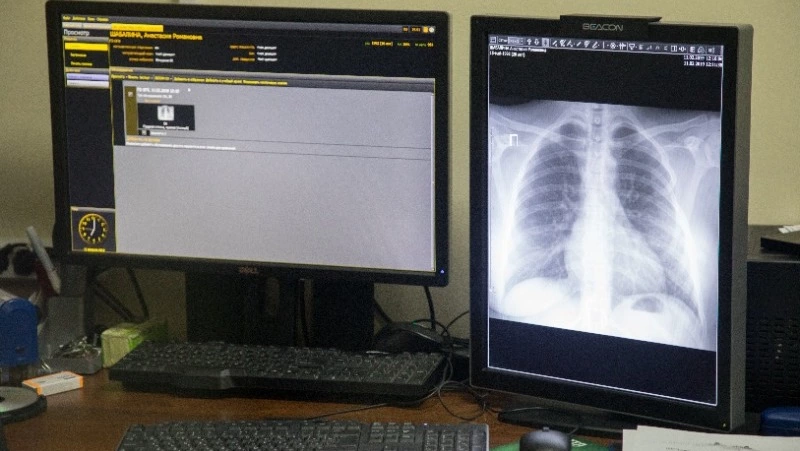

В Сахалинском областном противотуберкулезном диспансере для профилактических исследований и диагностики заболевания закуплено современное оборудование. С его помощью врачи проводят глубокое обследование, вовремя замечают у пациентов патологические изменения в легких и ставят диагноз.

«Мы используем в работе два рентгенологических аппарата — один для взрослых, а другой для детей. Есть компьютерный томограф на 64 среза и флюорографический аппарат. Более того, методы усовершенствовались — используются цифровые технологии. Снимки обследованных пациентов сейчас выводятся не на пленку, а на монитор. Хранятся они в центральном архиве медицинских изображений. При необходимости любой врач Сахалинской области может найти снимок того или иного пациента в базе», — пояснил заведующий рентгенологическим отделением противотуберкулезного диспансера Артур Плеско.